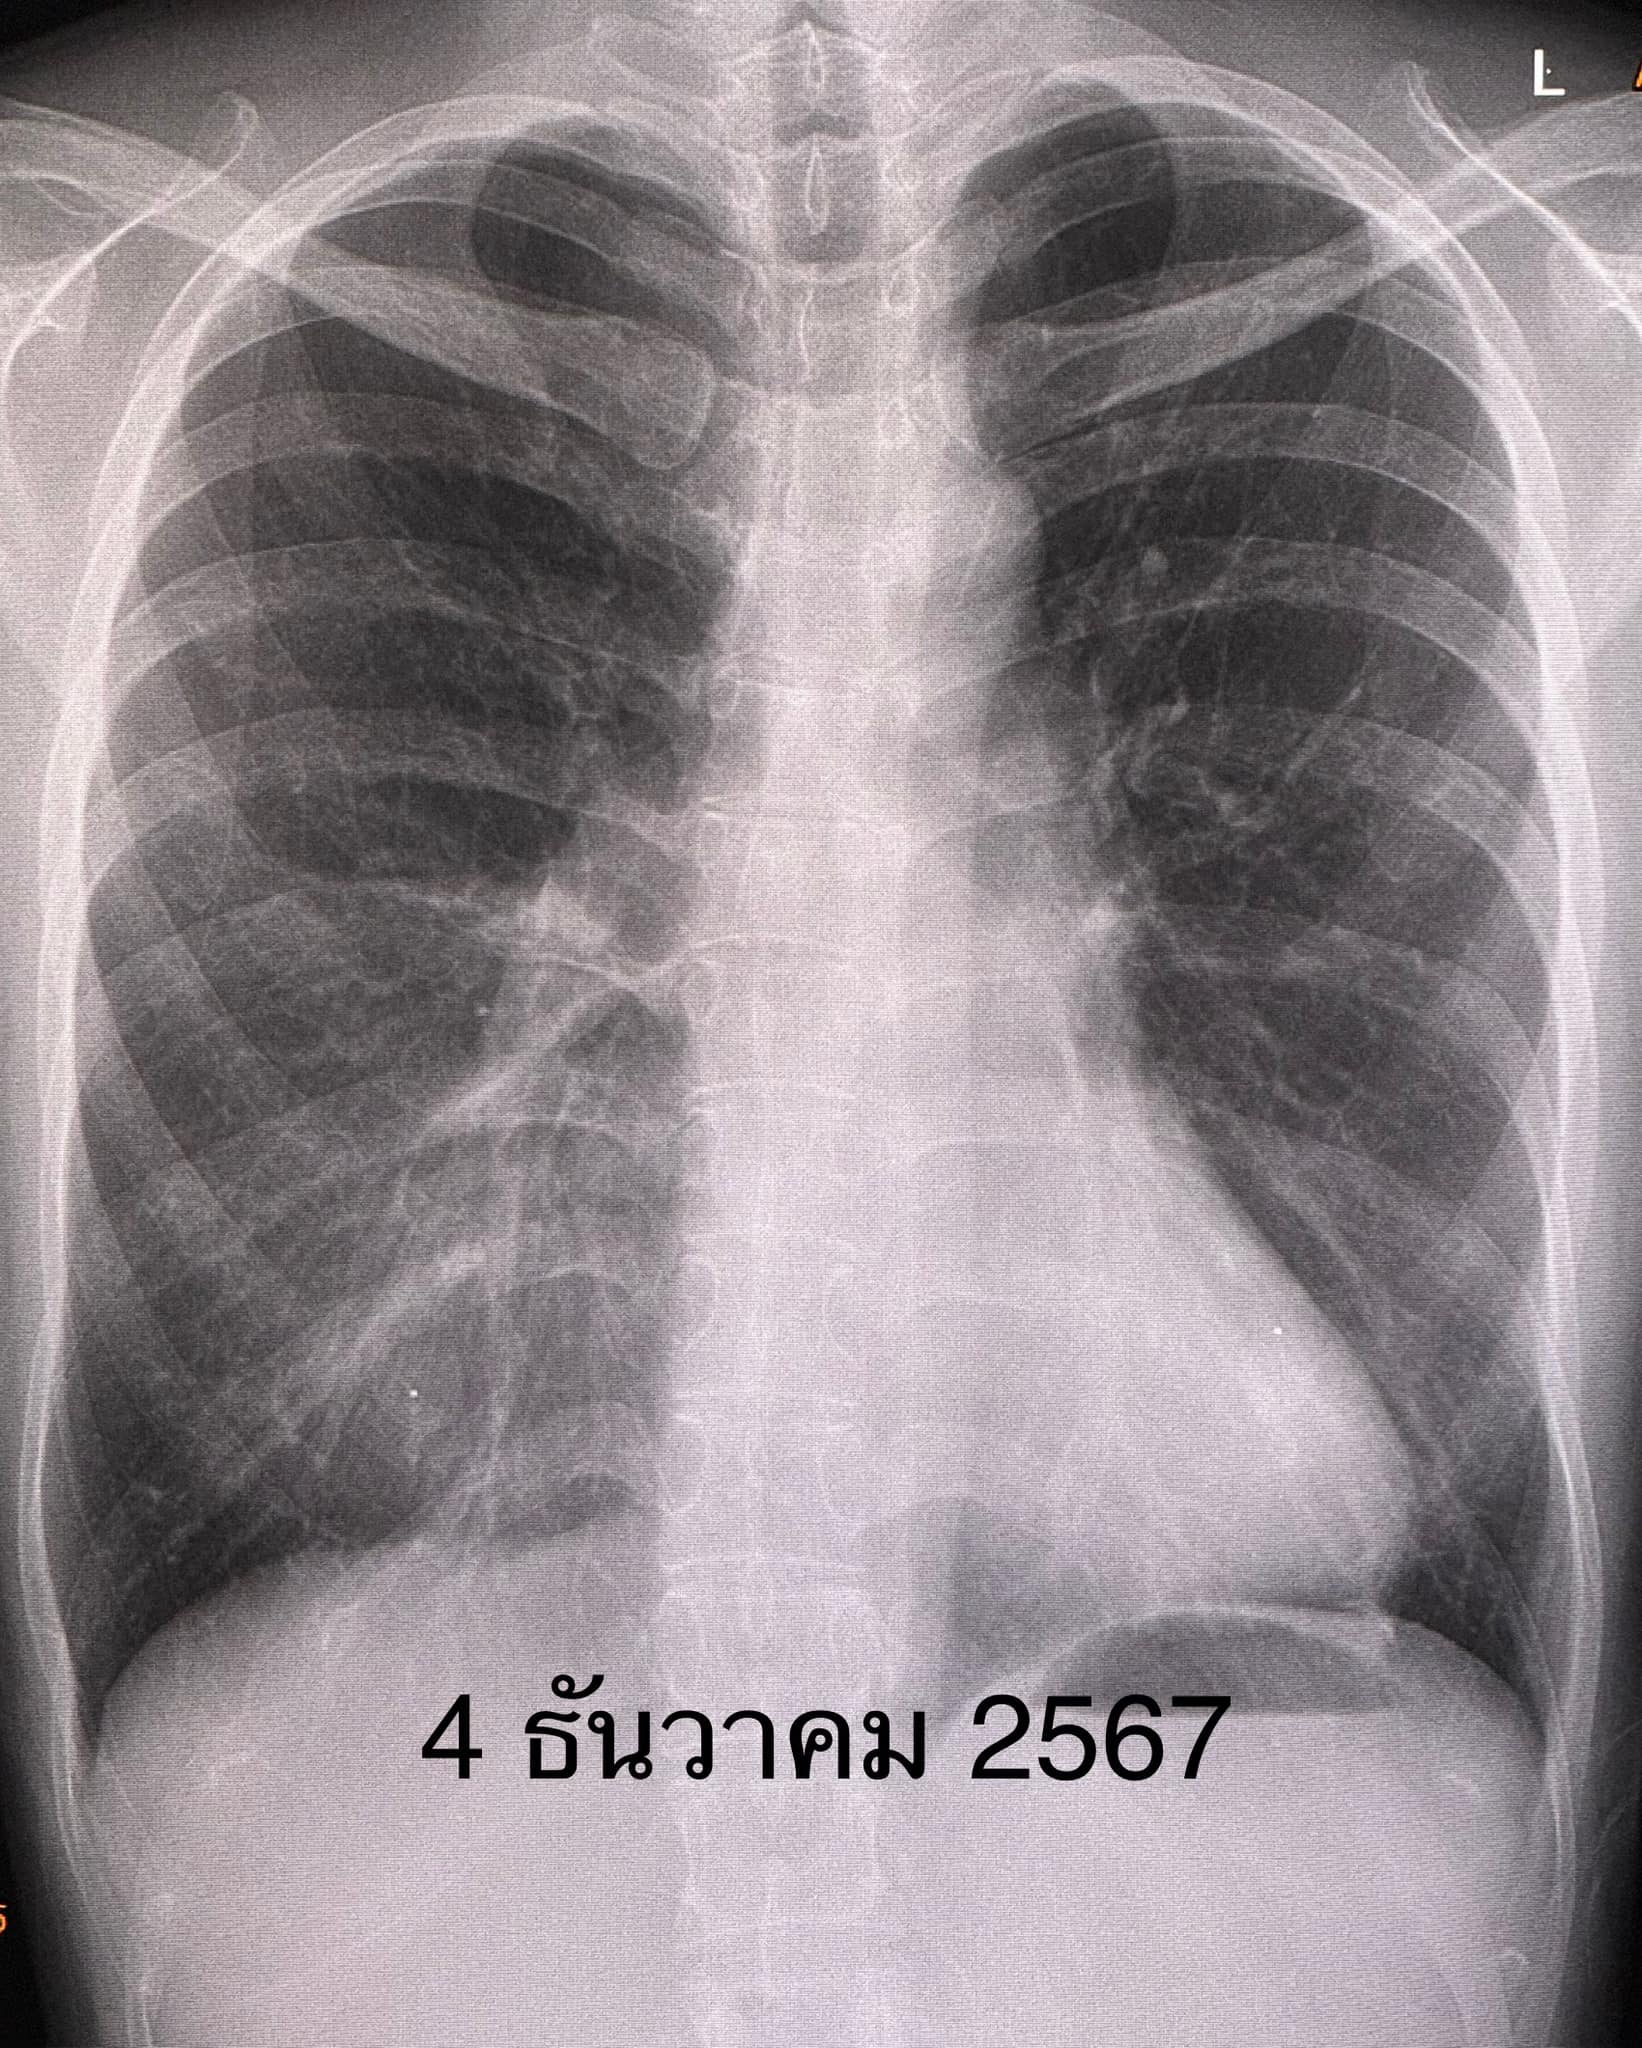

เอกซเรย์ปอดมีฝ้าขาวที่ปอดซ้ายด้านล่าง(ดูรูป ) คอมพิวเตอร์ปอดเห็นฝ้าขาวที่ปอดซ้ายด้านล่าง(ดูรูป) ทำสมรรถภาพปอดพบความจุของปอดลดลง เจาะเลือดค่าอักเสบของเลือดสูงเล็กน้อย ESR 31, hs-CRP 11.2, ANA positive 1:1280 Anti-MDA5 positive 3+, ค่าอักเสบของกล้ามเนื้อ CPK ปกติ 62

ผู้ป่วยได้วัคซีนไฟเซอร์เข็มที่ 3 เดือน ม.ค. 2566 เพราะกลัวว่าหากติดไวรัสโควิด-19 อาจป่วยรุนแรง เนื่องจากกำลังกินยากดภูมิคุ้มกัน ปรากฏว่า 5 วันหลังฉีดวัคซีนไฟเซอร์ ผื่นที่หน้า ข้อมือ ข้อศอก คอ หลังส่วนบน กลับมาเป็นมากขึ้น ไอ เหนื่อยเวลาออกกำลังกาย เอกซเรย์ปอดและคอมพิวเตอร์ปอดเห็นฝ้าขาวเพิ่มขึ้นที่ปอดด้านล่างทั้ง 2 ข้าง(ดูรูป)

ผู้ป่วยติดเชื้อไวรัสโควิดครั้งแรกวันที่ 5 ธค. 2566 มีอาการน้อยมาก ได้ยาโมลนูพิราเวียร์ หายเร็วทั้งๆที่กินยากดภูมิคุ้มกัน ไม่มีอาการหลังการติดเชื้อไวรัสโควิด ค่อยๆ ปรับลดยากดภูมิคุ้มกันลงเรื่อยๆ ผิวหนังกลับมาเป็นปกติ เอกซเรย์ปอด และคอมพิวเตอร์ปอดดีขึ้นเกือบปกติ(ดูรูป) ทำสมรรถภาพปอดความจุของปอดกลับมาปกติ วันที่ 17 ธ.ค. 2567 หลังจากรักษา 2 ปีกว่า ได้หยุดยากดภูมิคุ้มกันทุกตัวเหลือแต่ไฮดรอกซีคลอโรควิน กิน 1 เม็ดวันเว้นวัน ค่าอักเสบของเลือดปกติ ESR 8, hs-CRP 0.4